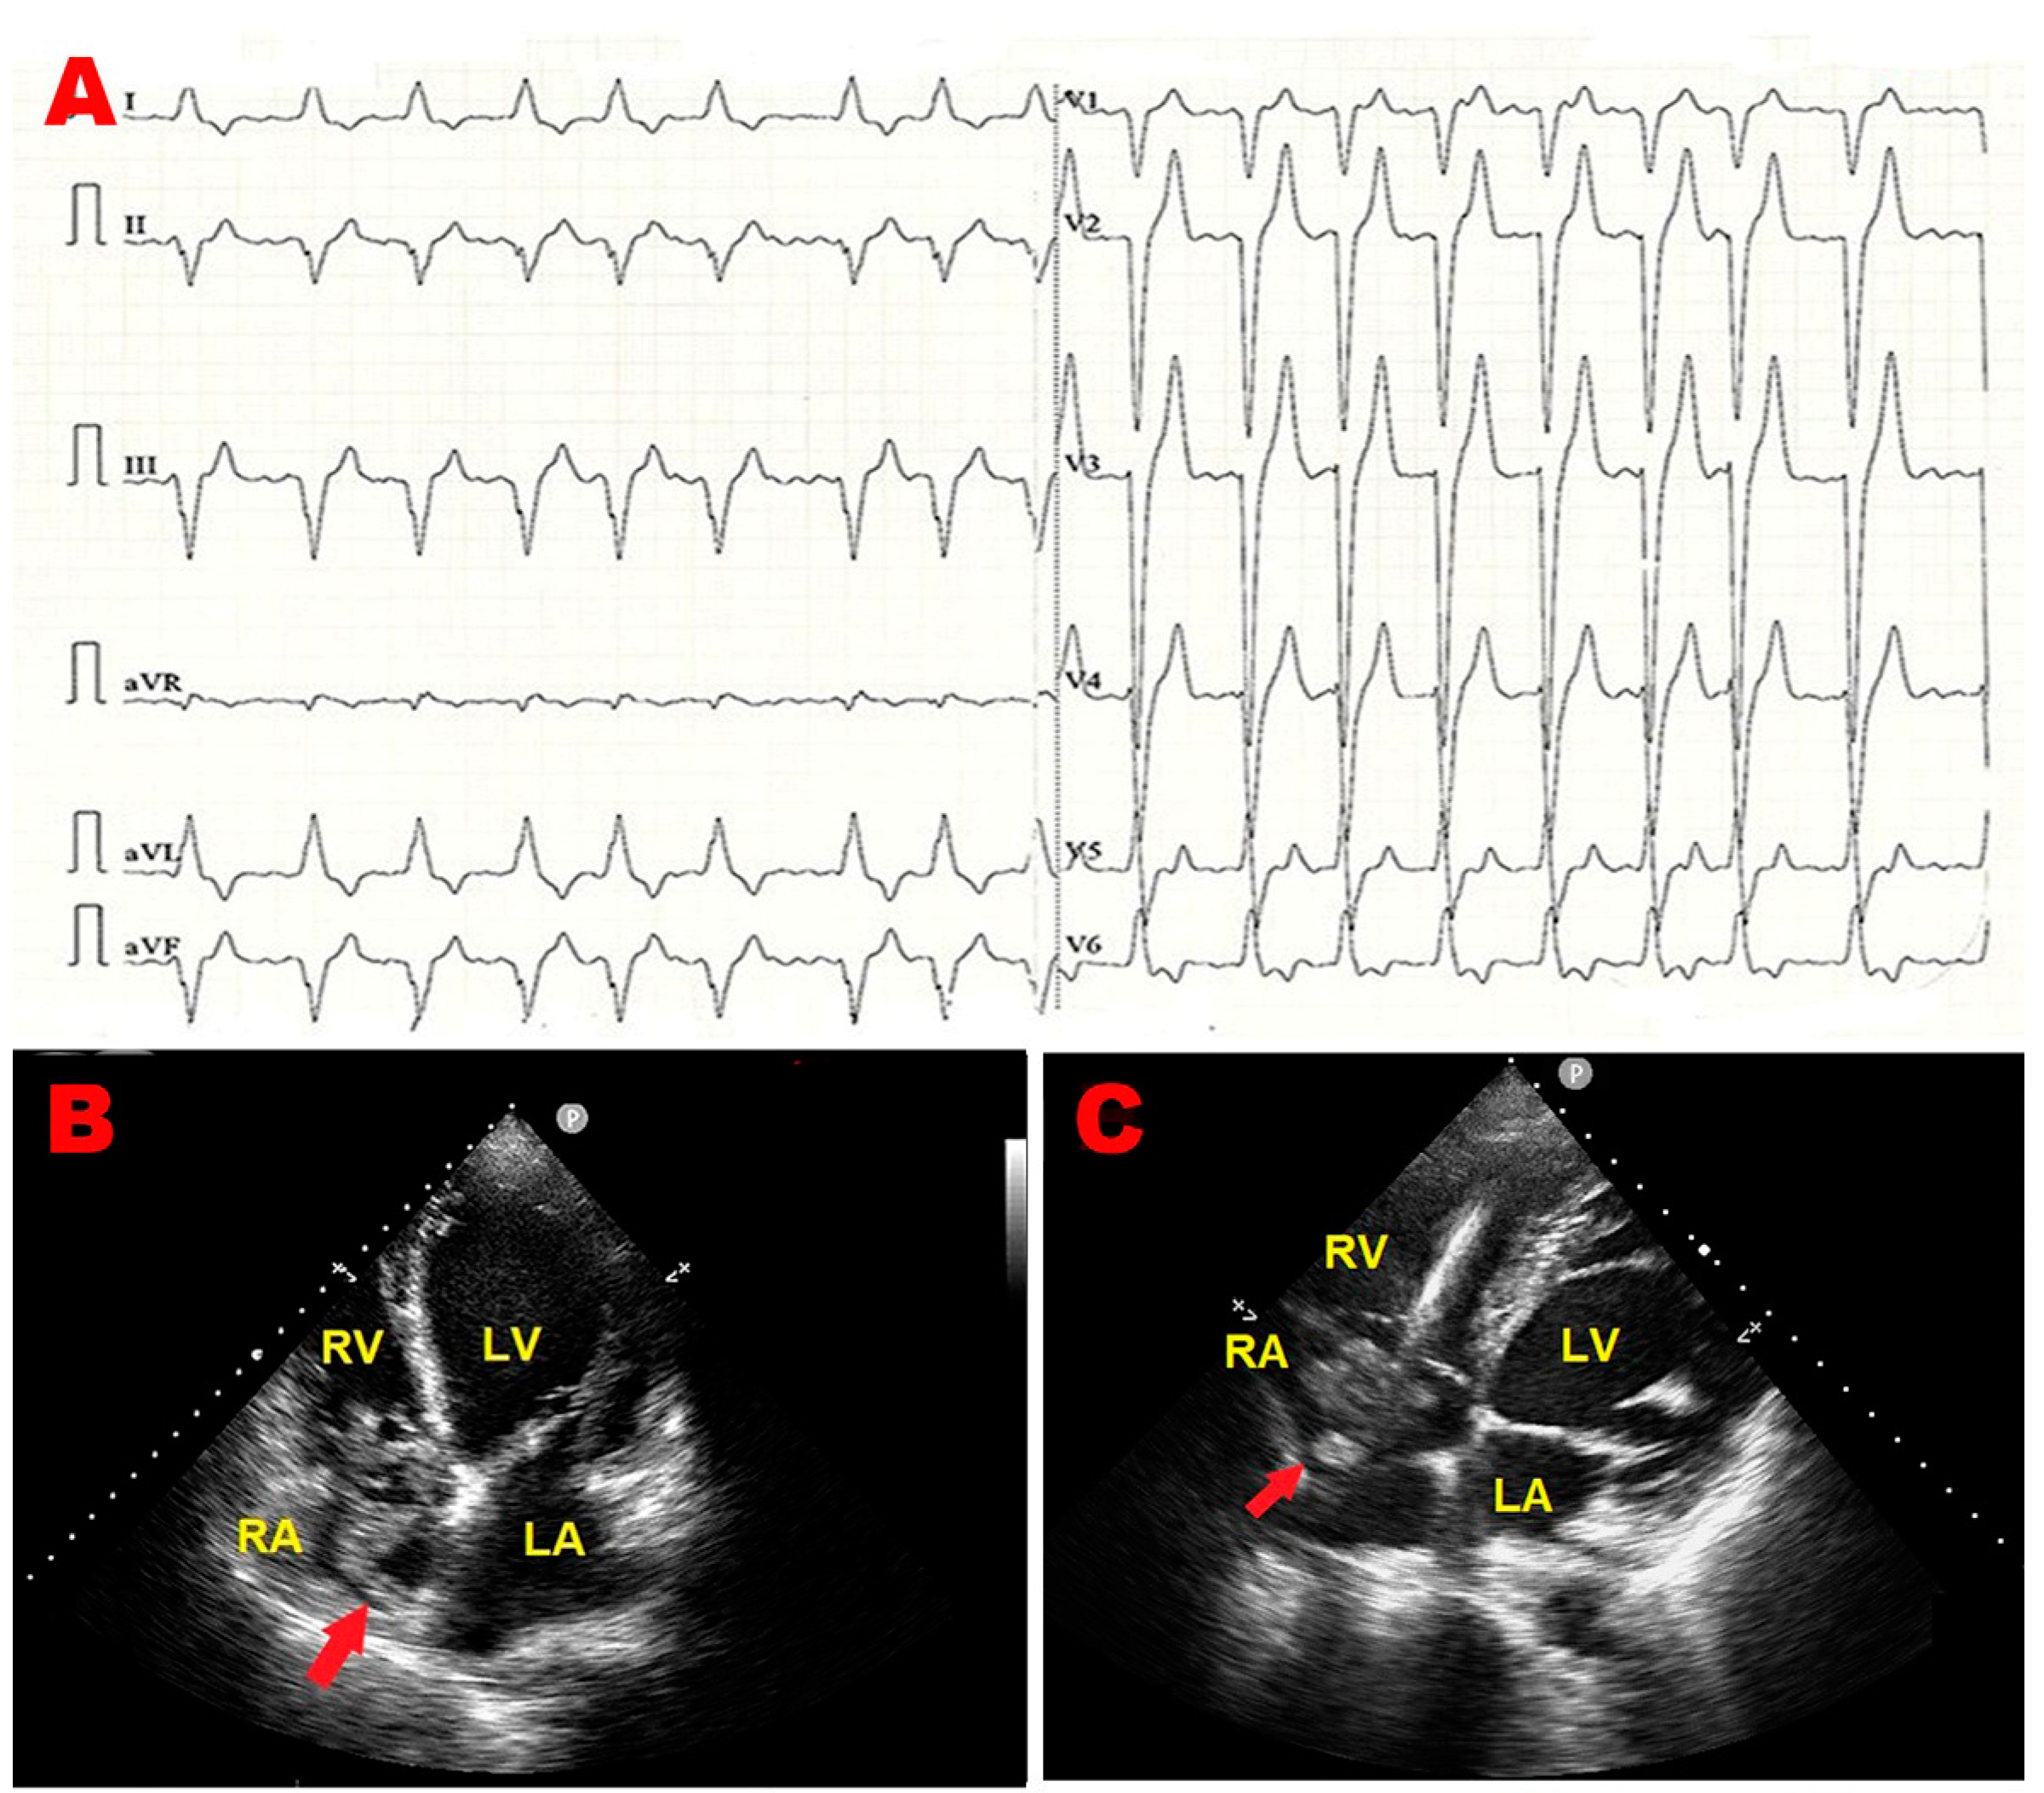

2.1. Clinical Case 1

2.2. Clinical Case 2